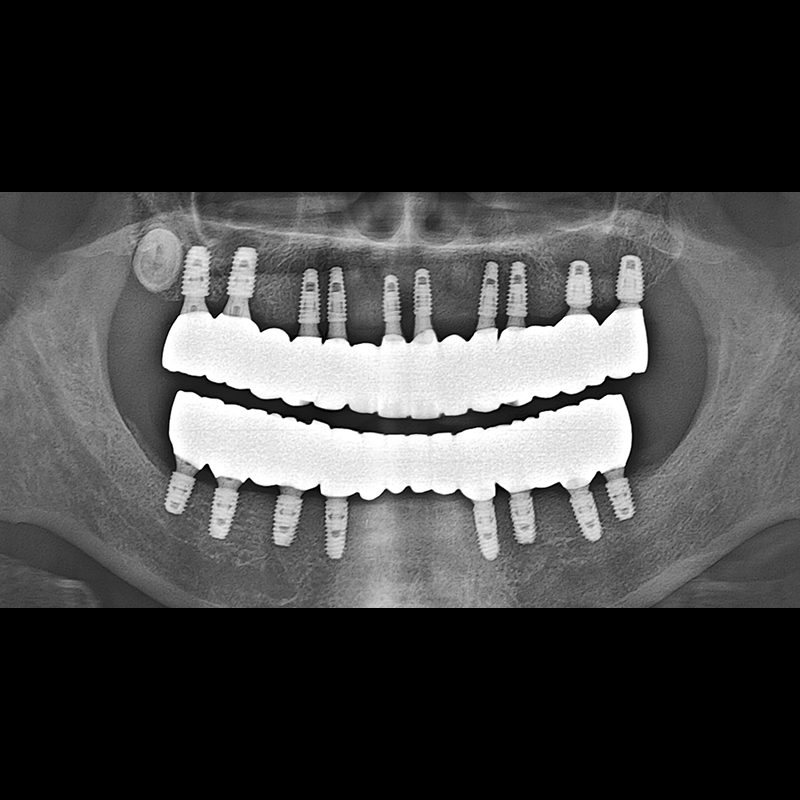

IMPLANT

BEFORE AFTER

Implant before and after 2025.05.30

Implants were placed in the missing tooth and in the tooth position where it was difficult to save.